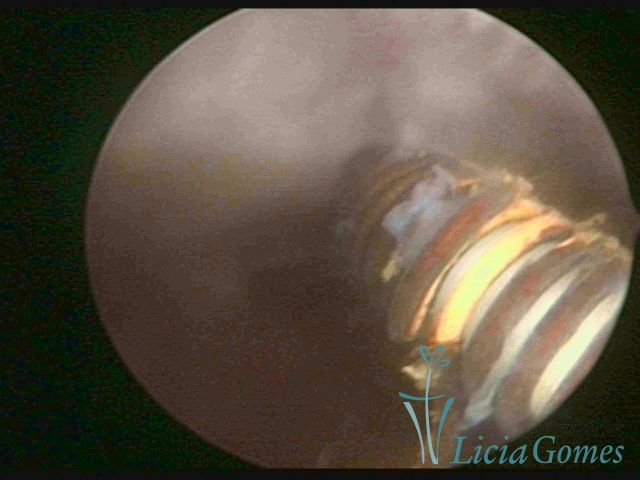

DIU perfurado miométrio